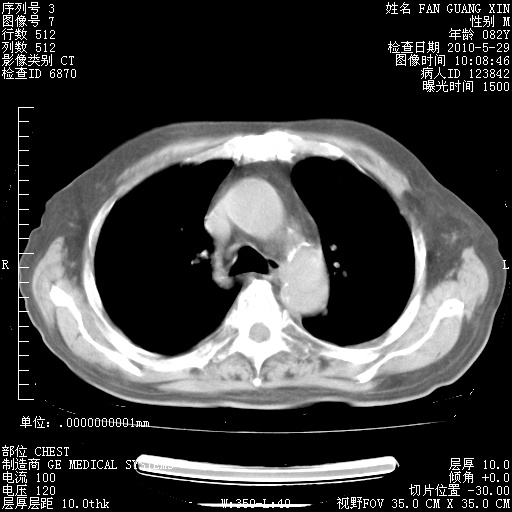

再治疗10天后的肺部CT 纵膈窗